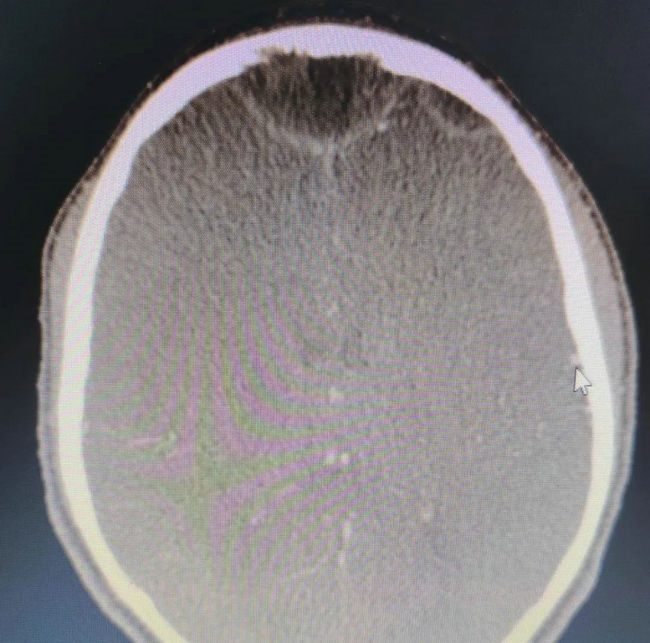

由于当地经济条件和医疗水平落后,很多患者无钱医治疾病,有的肿瘤患者肿瘤组织甚至长满腹腔,年幼的孩子肺脓肿能够穿破胸腔至体表,鼻窦炎的儿童炎症能蔓延到颅内……医生的缺乏也导致诊断报告几个月迟迟出不来,感到痛心的同时,他加班加点,加快影像诊断,马不停蹄地阅片、出报告,用了不到两周时间将前期累计的患者悉数完成报告。